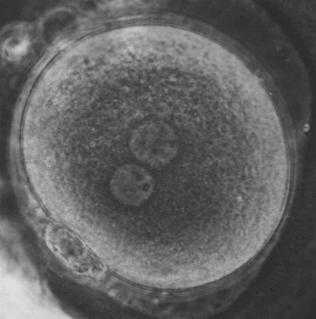

1. Ovo ou Zigoto

1. Célula diploide resultante da união dos núcleos de duas células.

2. ³ Blastula Humana ( Blastocisto )